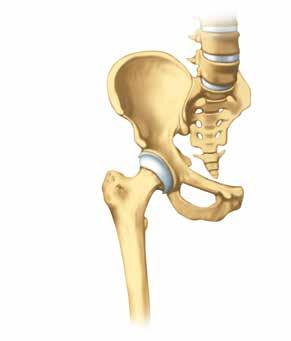

Os du bassin

Cotyle

Bourrelet articulaire

Tête de l’articulation

Col du fémur

Fémur

partielle est prise lors de l’entretien avec le ou la médecin. La durée d’hospitalisation totale est d’environ 6–10 jours pour une opération du genou et de 4–7 jours pour une opération de la hanche.